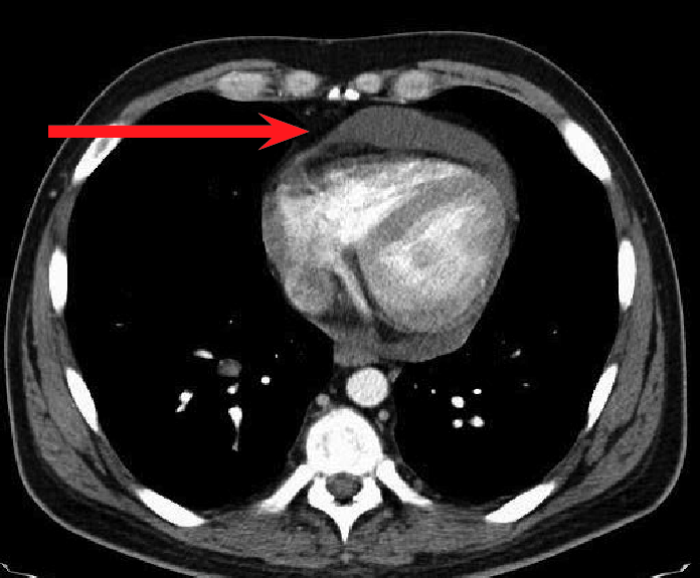

經(jīng)檢查,徐大爺被確診為結(jié)核性心包炎。

“該病起病隱匿,常有心外原發(fā)性結(jié)核病灶或同時有其他漿膜腔結(jié)核性積液存在,易出現(xiàn)長期低熱、盜汗、疲乏無力等癥狀,多無胸痛,易轉(zhuǎn)為慢性,最后形成縮窄性心包炎。”感染科翁亮亮醫(yī)生介紹,結(jié)核性心包炎為重癥結(jié)核病之一,對患者生命、生活質(zhì)量均可造成嚴(yán)重影響。

確診結(jié)核性心包炎后需要規(guī)律治療,防止病程進(jìn)展到縮窄階段,降低死亡率。由于徐大爺基礎(chǔ)疾病較多,感染科團(tuán)隊(duì)為其量身定制了個體化抗結(jié)核治療方案。